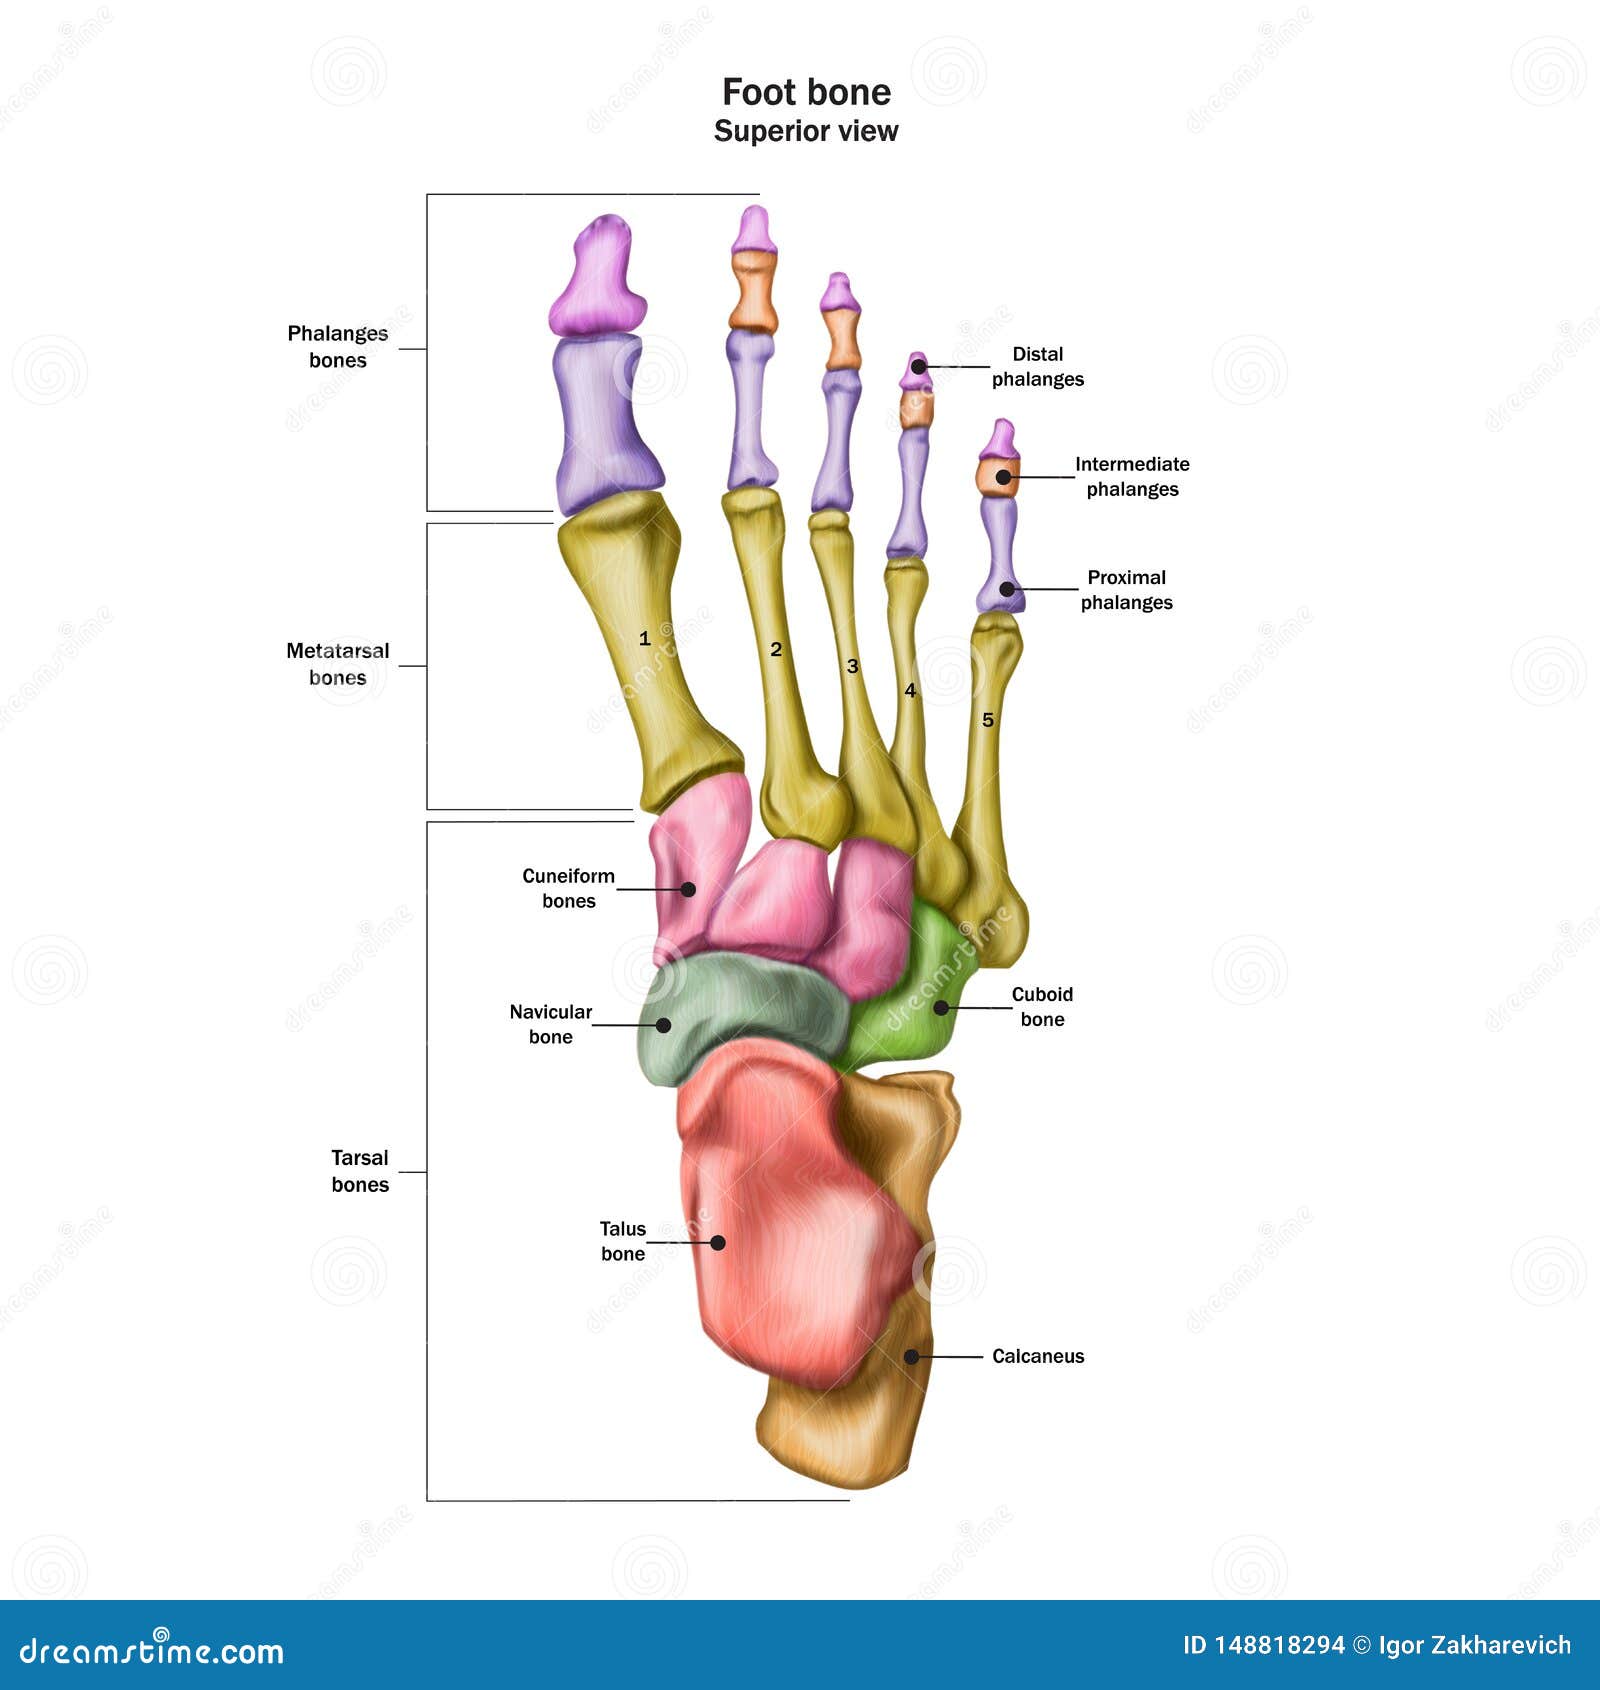

Illustrazione Di Anatomia Del Piede Umano Illustrazione Di Stock

it.dreamstime.com3d Illustration Of Skeleton Foot Bone Anatomy Stock Illustration

it.dreamstime.com3d Illustration Of Skeleton Foot Bone Anatomy Stock Illustration

www.dreamstime.combones anatomie pied nom humain rieure sup humaine tous

www.dreamstime.combones anatomie pied nom humain rieure sup humaine tous